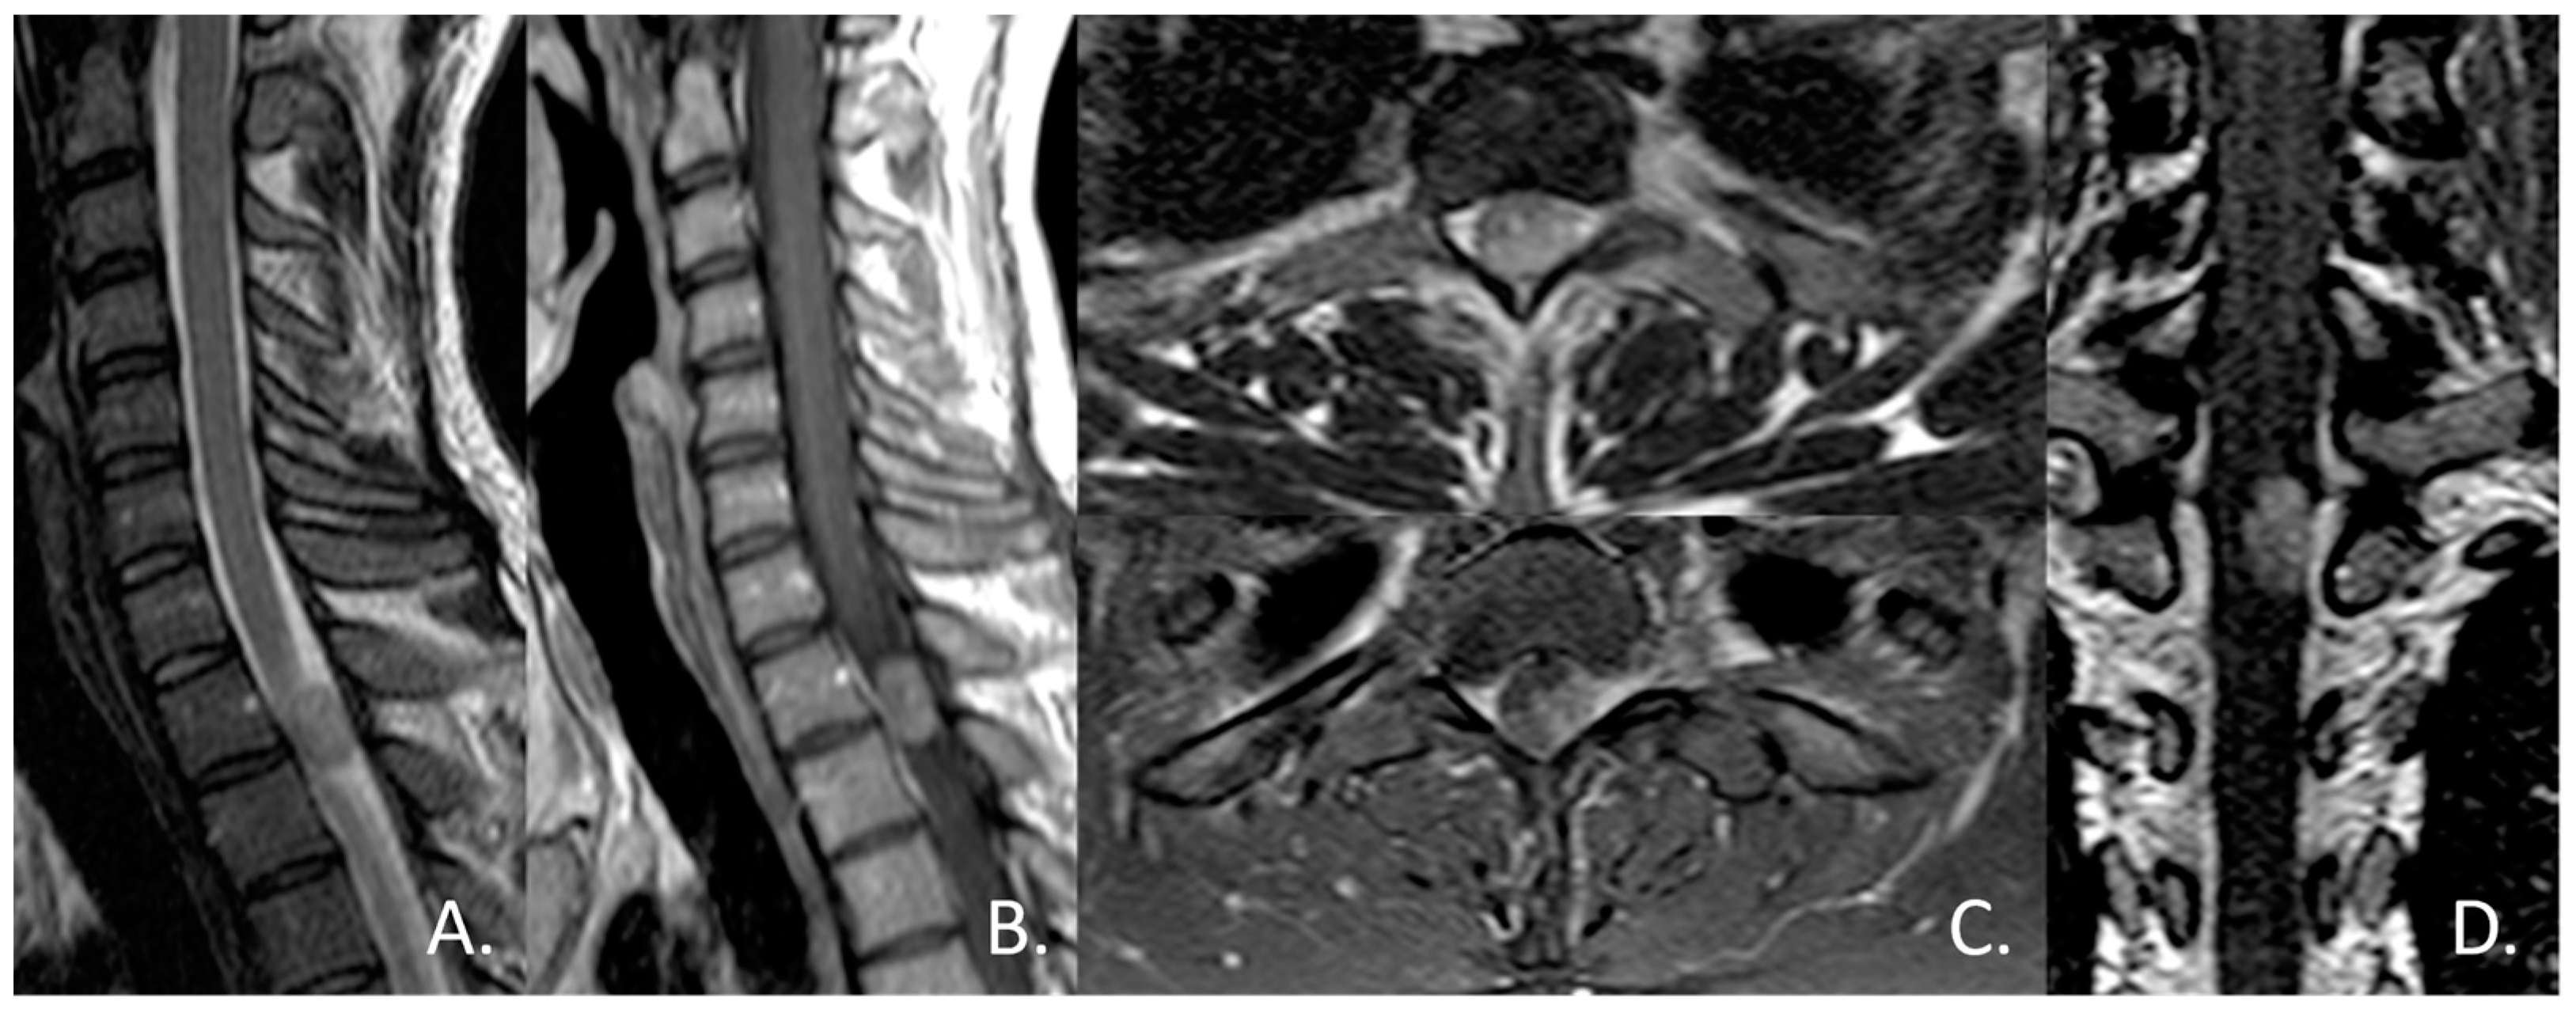

3.2. Unexpected Radiological Features in a Case of SpDG H3K27M

4.2. Radiological Finding